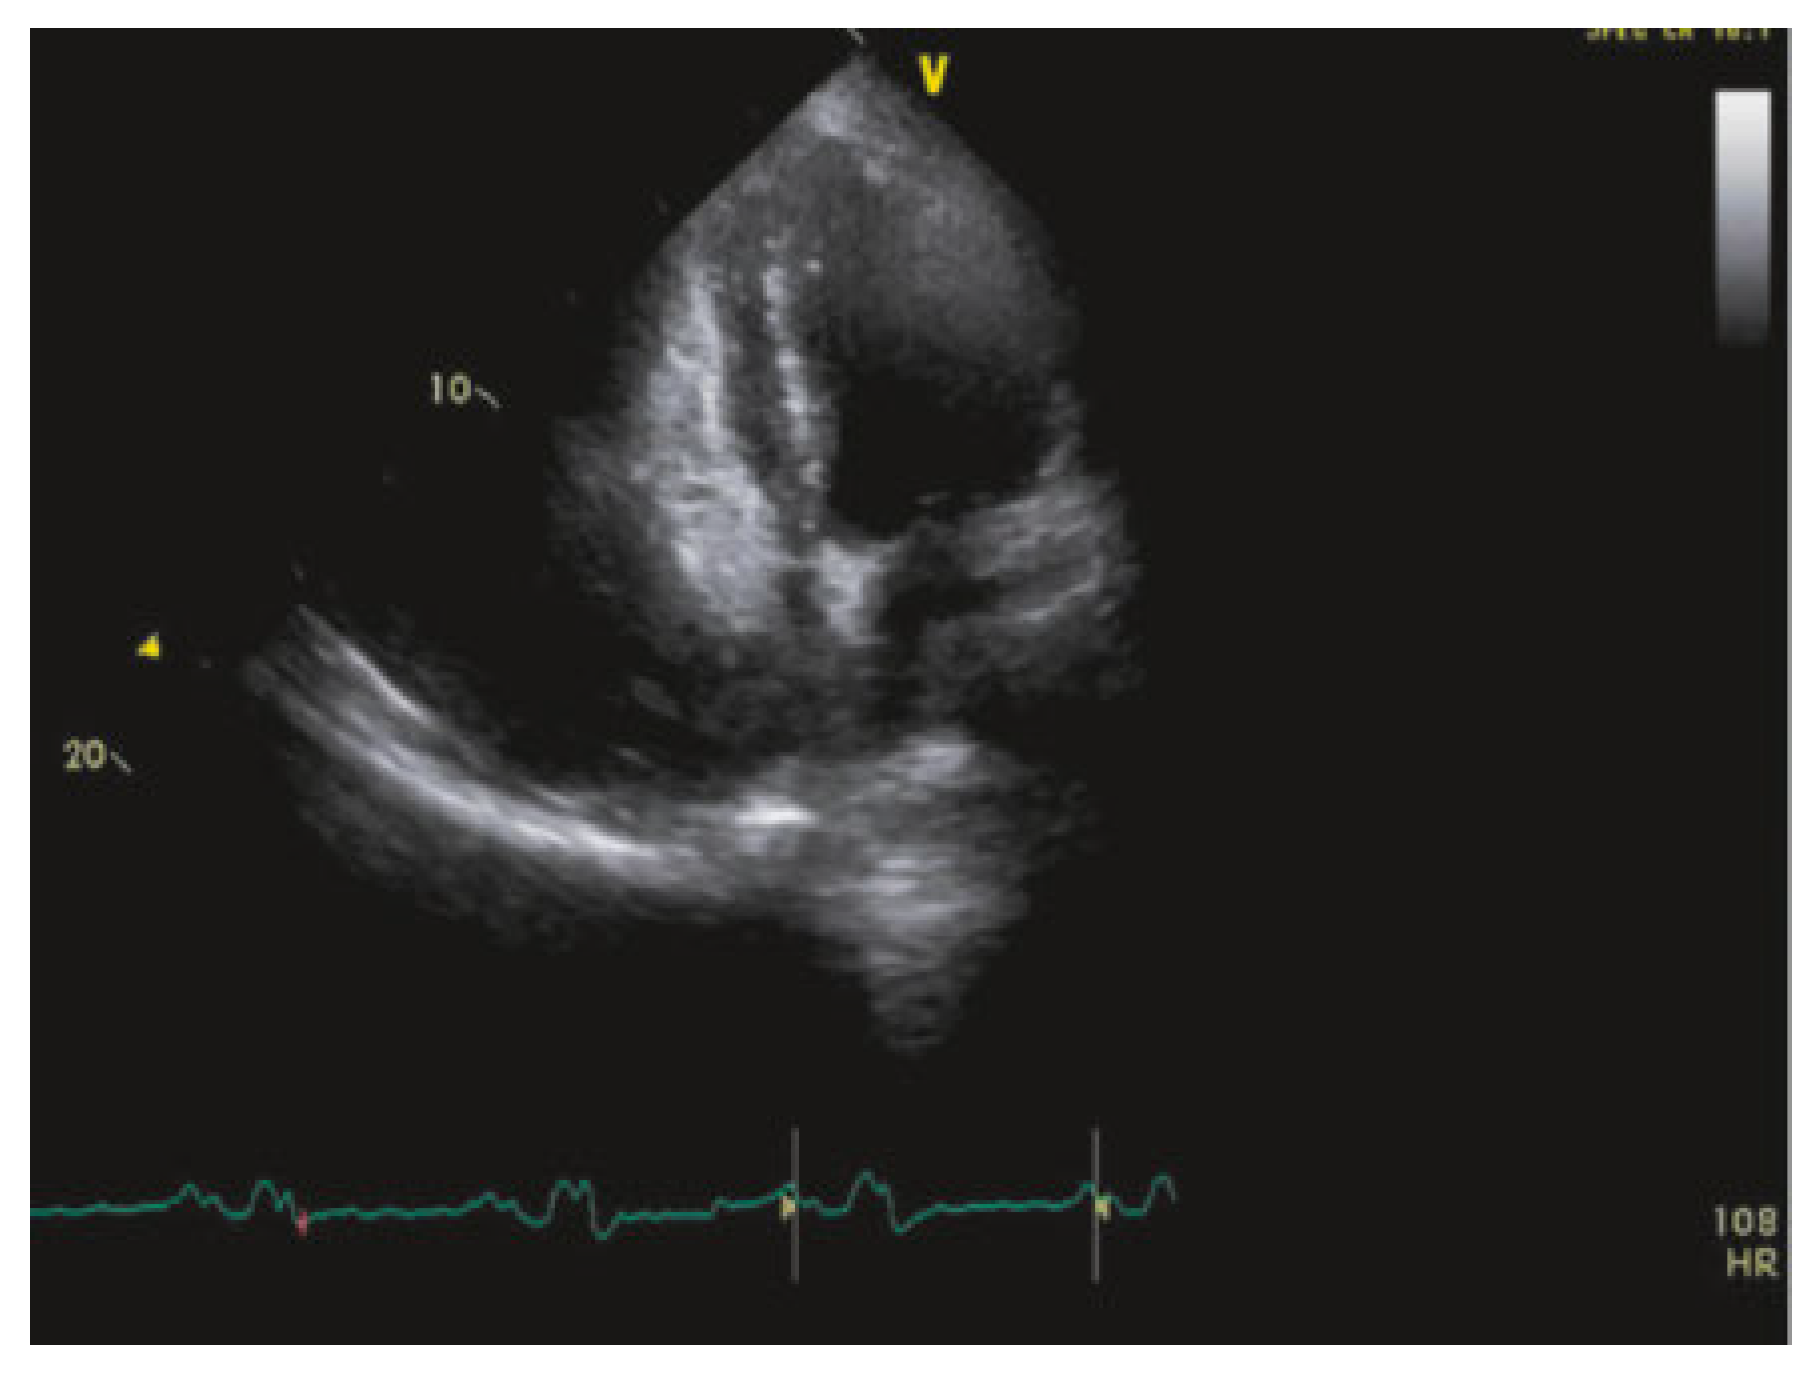

Pulmonary Embolism

Figure 7). Hence, transthoracic echocardiography should not be performed routinely in haemodynamically stable patients (not high-risk) when pulmonary embolism is suspected. On the other hand, echocardiography has an important value in haemodynamically unstable patients when CTangiography is not immediately available or when only bedside tests are possible in critically ill patients. Furthermore, echocardiography is needed for risk assessment and for guiding management strategies in haemodynamically stable patients at intermediate risk.

The main indirect echocardiographic findings in pulmonary embolism include dilatation of right-sided cardiac cavities and decreased systolic function of the right ventricle. An interesting additional parameter consists of regional wall motion abnormalities of the right ventricular free wall, known as McConnell’s sign; patients with acute pulmonary embolism frequently display normal or hyperdynamic contraction of the right ventricular apex, while the remainder of its free wall is hypokinetic or akinetic (

Figure 8). Systolic pulmonary artery pressure may also be estimated if tricuspid regurgitation is present. Rarely (<4%) specific echocardiographic findings can be made such as the presence of emboli in right-sided cardiac cavities [

12,

36].